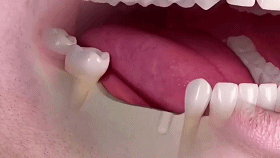

多顆牙種植

相比傳統(tǒng)固定義齒和活動(dòng)義齒,種植牙是醫(yī)學(xué)界公認(rèn)的理想修復(fù)方式,被譽(yù)為“人類的第三副牙”。相比活動(dòng)假牙不舒服、難清洗、容易引起口腔黏膜病變,種植牙更穩(wěn)固耐用,舒適美觀,咀嚼功能好,一次種植,即可重獲好口福!種植牙不僅是中老年人的專利,年輕人因意外、牙病等造成的單顆、多顆牙齒缺失,也能夠通過種植牙進(jìn)行修復(fù)調(diào)節(jié),重獲幸福笑容。